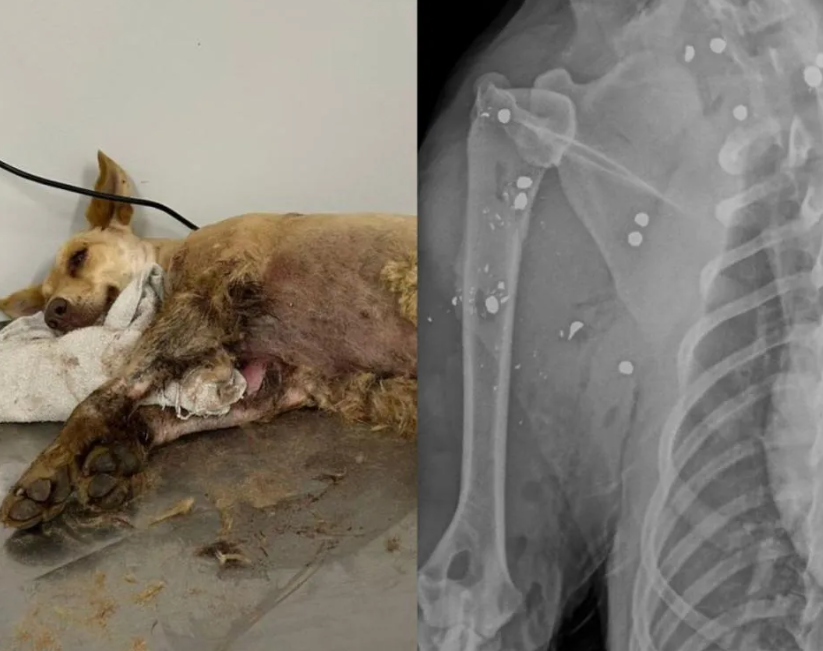

Uma cadela foi resgatada com mais de 20 projéteis de chumbinho pelo corpo após uma denúncia de maus-tratos no bairro Belchior Central, em Gaspar, no Vale do Itajaí. O caso mobilizou a Diretoria do Bem-Estar Animal nesta segunda-feira (27).

A equipe de resgate levou a cadela imediatamente a uma clínica veterinária, onde ela passou por uma cirurgia de emergência. O estado de saúde é estável, e o animal segue internado recebendo cuidados intensivos.

Foto: Divulgação/Prefeitura de Gaspar